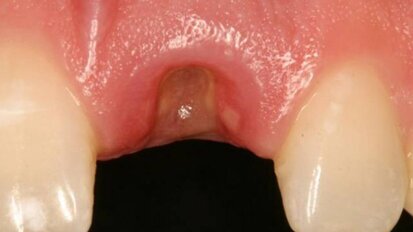

Les propres cellules souches du patient récoltées et transplantées dans sa mâchoire.

Le Dr Ivan Ho, dentiste en Californie du Sud et fondateur de Platinum Dental, a récemment effectué une greffe de cellules souches ...